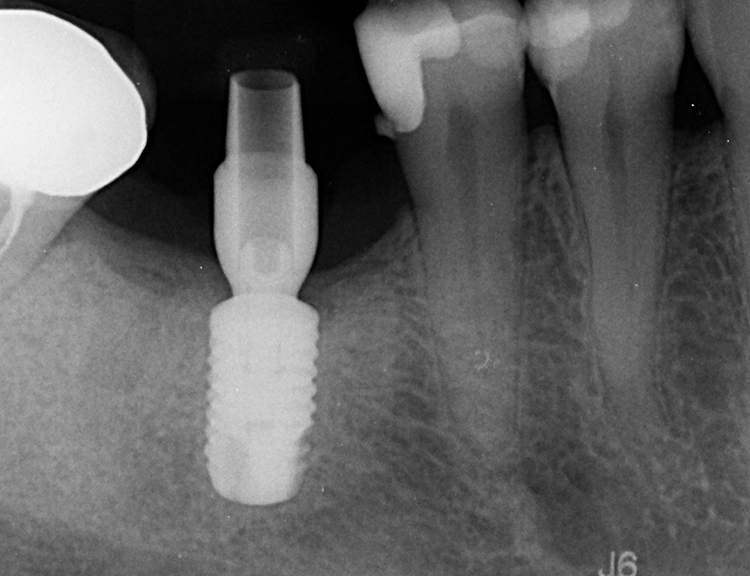

Drei Monate nach der Extraktion des nicht erhaltungswürdigen Zahnes 46 wurde im Januar 2021 eine DVT angefertigt (Abb. 2) und es wurden Ober- und Unterkiefer abgeformt. Für die Planung der Bohrschablonen (Fremdlabor) erfolgte die Digitalisierung der Modelle mit einem Laborscanner im Eigenlabor, anschließend wurden die Daten an den Planungspartner zur Herstellung der Bohrschablonen übermittelt. Dort erfolgte die digitale Vorplanung der Implantatposition und der prothetischen Versorgung mit der Planungssoftware coDiagnostiX (dental wings) (Abb. 3 und 4).

Die Dokumentation des Implantatsitzes erfolgte mit einer postoperativen Panoramaschichtaufnahme (Abb. 16). Nach der gedeckten Einheilung erfolgte im Juni 2021 die geschlossene Implantatabformung mit Impregum. Abbildung 17 bis 25 zeigt den Ablauf von der Inzision drei Monate nach Implantation bis zum Einsetzen des Hybrid-Abutments mit Titan-Klebebasis und Zirkonaufbau bis zur finalen Zirkonkrone, die aufgrund einer Erkrankung der Patientin etwas später als vorgesehen im Juli 2021 eingegliedert werden konnte. Die Versorgung der insuffizienten Einzelkrone 47 erfolgt auf Patientenwunsch zu einem späteren Zeitpunkt.